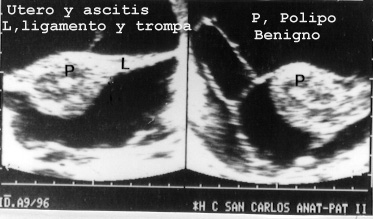

Los órganos femeninos son también visibles cuando hay ascitis y se pueden visualizar pólipos (Fig 39) o miomas etc.

En general las autopsias en nuestro medio pocas veces encuentran datos no esperados por los clínicos en el aparato genital femenino pues las mujeres suelen ir con frecuencia al ginecólogo. De nuestra serie llama la atención el pólipo presentado y un caso diagnosticado en vida de adenocarcinoma de ovario. En verdad la masa observada en vida en ecografía como de ovario pudimos demostrar en ecopsia y autopsia que era un útero con miomas de localización lateralizada El estudio histológico de la masa demostró que era un mioma. En cambio Los estudios postmortem demostraron un tumor de colon con metástasis en hígado y peritoneo.